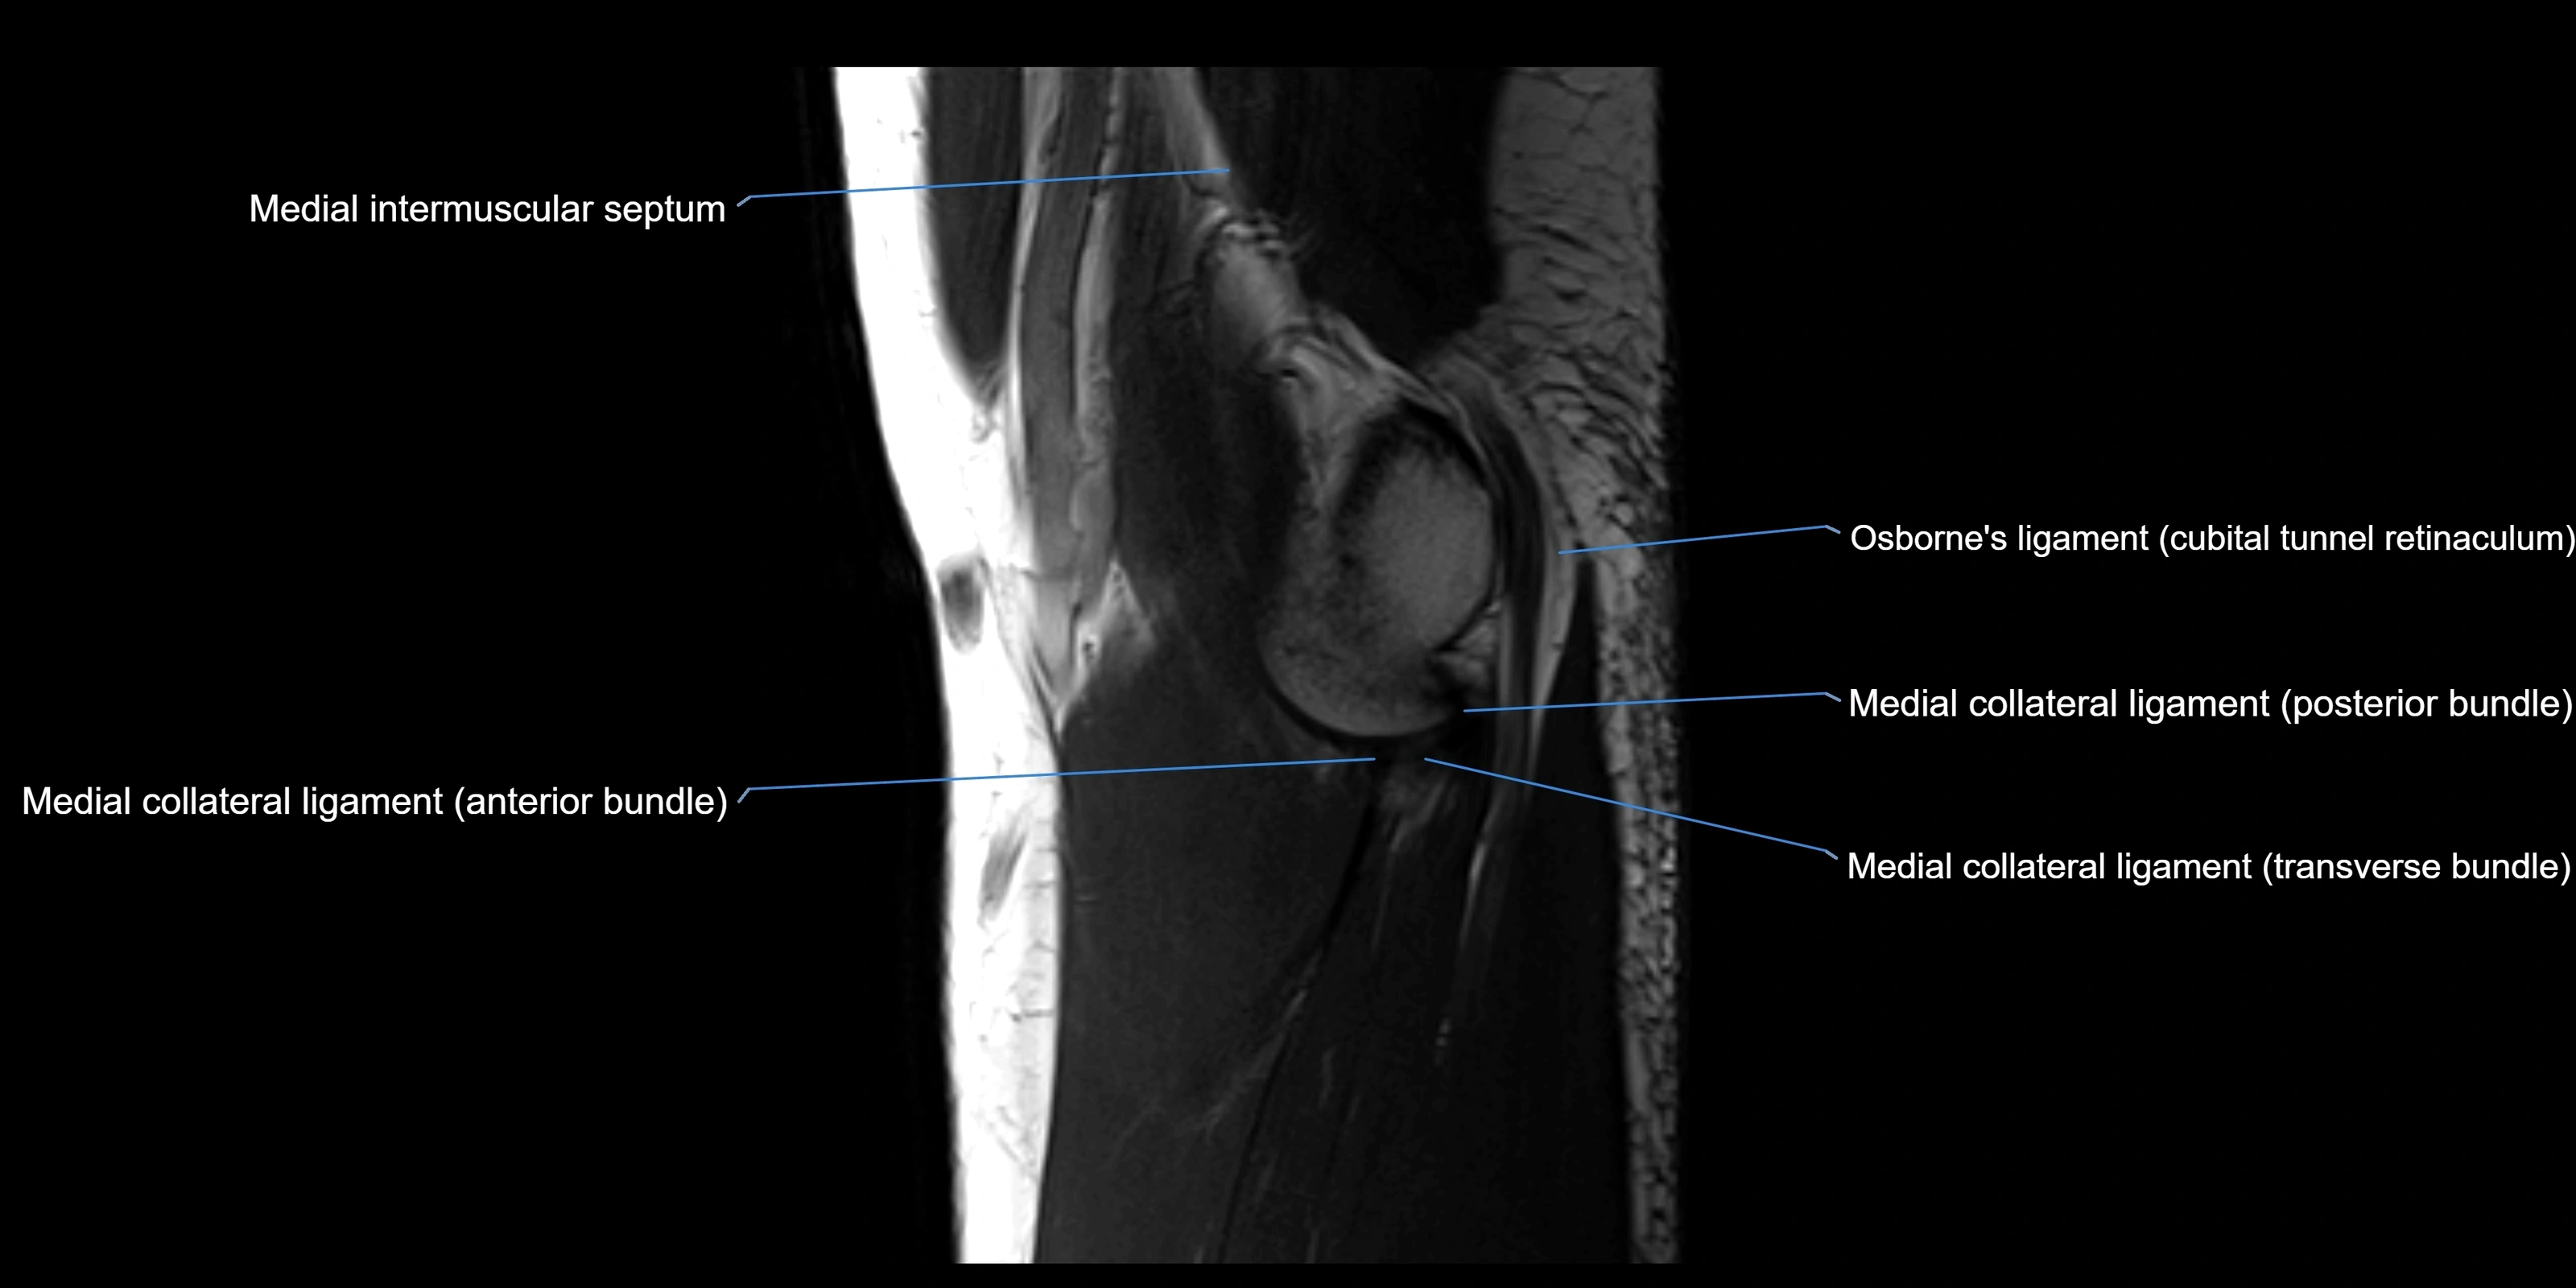

MRI Appearance

T1-weighted images:

• Ligament: low signal intensity (dark), appearing as a continuous band around the radial head.

• Adjacent fat and marrow: bright, creating contrast with the ligament.

• Thickening or disruption indicates injury or fibrosis.

• Joint capsule and synovium seen as thin low-signal lines contiguous with ligament margins.

T2-weighted images:

• Ligament: low signal (dark) with clear delineation from joint fluid.

• Fluid or edema: bright hyperintense, separating or surrounding the ligament in partial tears.

• Complete tear: discontinuity or non-visualization of ligament fibers, often with joint effusion.

MRI images

image